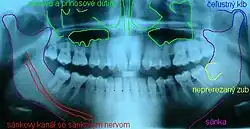

Oligodontie bei einem fünfjährigen Mädchen infolge einer Hypohidrotischen ektodermalen Dysplasie: Im Oberkiefer ist kein bleibender Frontzahn angelegt. Daher persistieren die Milchzähne. Im Unterkiefer fehlen auf jeder Seite drei bleibende Zähne, die Zähne 31 und 41 (mittlere Schneidezähne) sind extrem retiniert. Eine (Nicht)-Anlage der Weisheitszähne kann noch nicht beurteilt werden.